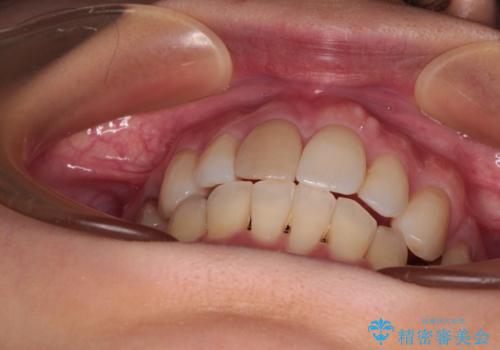

- 口を閉じたときに飛び出してしまう上顎前歯を気にして来院された患者様です。

上下の咬み合わせは上顎歯列全体が歯1本分前にずれている状態であり、さらに上顎歯列はV字型に尖っていたため、上下前歯は全く接触していない状態でした。

上顎左右第一小臼歯を抜去して、ワイヤー装置にて口元の突出感を改善するよう矯正治療を行うこととしました。